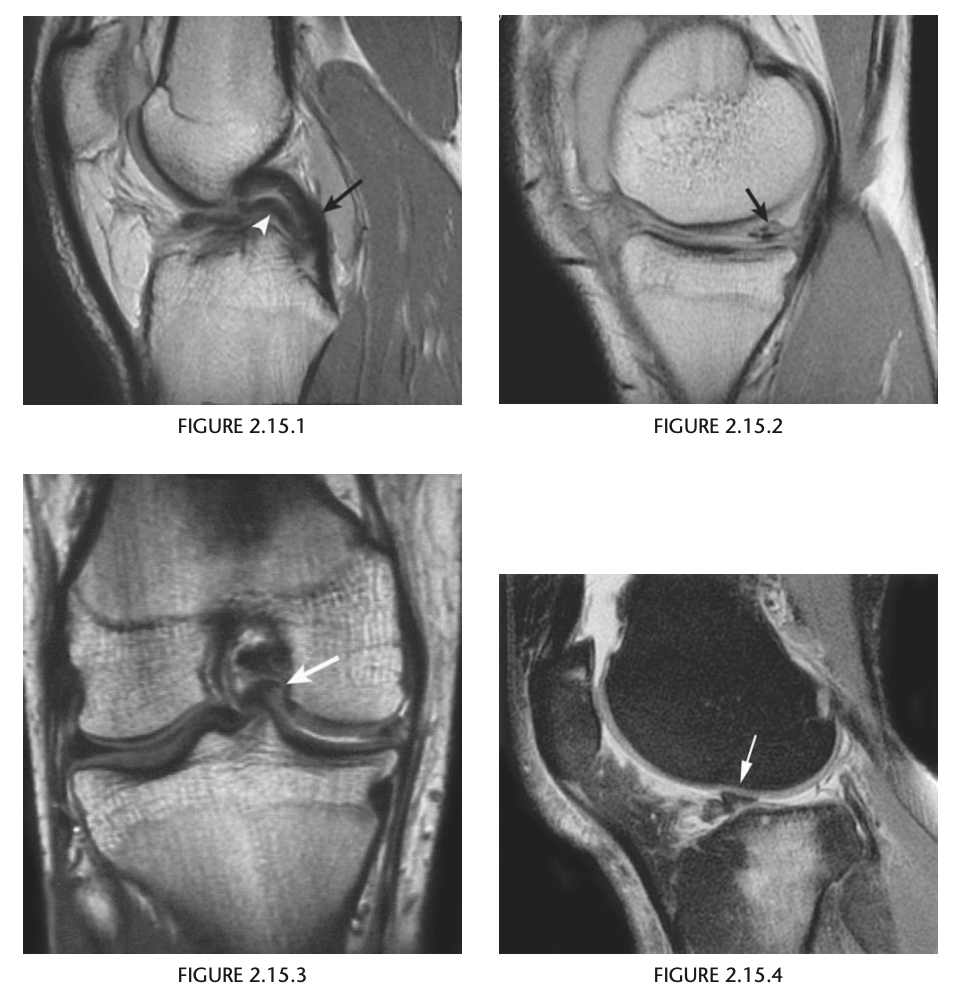

14

A 19-year-old man with worsening pain in the right knee after a recent injury

A sagittal proton-density MR image of the

right knee (Fig. 2.15.1) shows a normal posterior cruci-

ate ligament (PCL, arrow) with an apparent second PCL

underneath (i.e., “double-PCL” sign; arrowhead). A sag-

ittal proton-density image through the edge of the

medial meniscus shows increased signal intensity in the posterior horn of the medial meniscus. diminished visualization of the anterior horn,

and lack of the characteristic bow-tie appearance of the meniscus at this site. A corresponding coronal proton-

density image reveals the displaced meniscal fragment

in the intercondylar notch.

Displaced bucket-handle tear of the

medial meniscus

Bucket handle tear is a longitudinal meniscal tear with central, unstable fragment migrates into

the intercondylar notch.

As seen arthroscopically,

the migrated fragment represents the handle of the

bucket, and the portion of the meniscus remaining

in situ represents the bucket

On 4-mm sagittal images, the medial menis-

cus should have a bow-tie appearance on at least

three consecutive MR slices. If the meniscus is not

seen on all these slices, then the coronal images

must be scrutinized to confirm that the meniscus

is intact.

double-PCL sign is produced by displace-

ment of the meniscal handle fragment into the in-

tercondylar notch, where it comes to rest anterior

and inferior to the PCL.

“flipped meniscus” sign. This

sign consists of a shortened posterior horn with

an abnormally tall anterior horn (>6 mm) on sag-

ittal images.

Figure 2.15.5, in which there is a

full-thickness ACL tear causing a double-PCL sign

(arrowheads) and a bucket-handle tear of the menis-

cus that is flipped anteriorly, causing an abnormally

tall meniscal anterior horn (arrow).